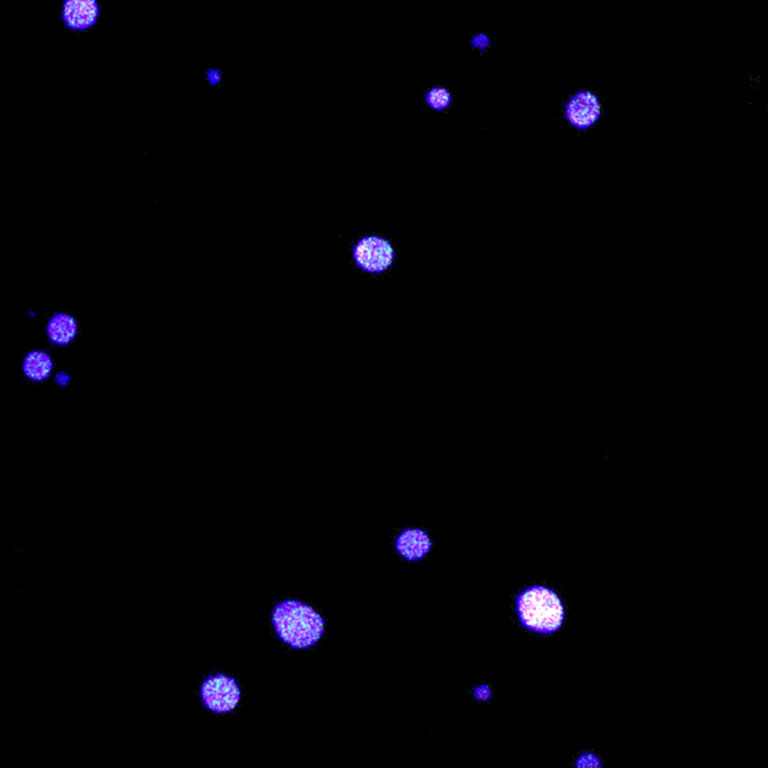

Spectral Scanning Confocal Fluorescence Microscopy

RNA interference (RNAi) therapy allows researchers to silence the expression of nearly any gene that leads to the production of a disease-associated protein. Although this novel method provides unprecedented therapeutic potential, effective packaging and delivery of short RNA sequences which facilitate RNAi remains a challenge due to their poor stability in the body and inefficient cellular uptake. Koch Institute researchers in the Hammond Lab are engineering RNAi technologies which consist of short RNAi sequences that self-assemble into sponge-like nanoparticles, each containing half a million drug molecules in a space more than 100 times smaller than the width of a human hair. These RNAi nanomedicines, which exhibit high stability and efficient cellular delivery, are currently being investigated as a means of silencing cancer-associated genes. These images demonstrate the morphology of RNAi nanosponges and also confirm the existence of fluorescently-labeled small interfering RNA within the structures.